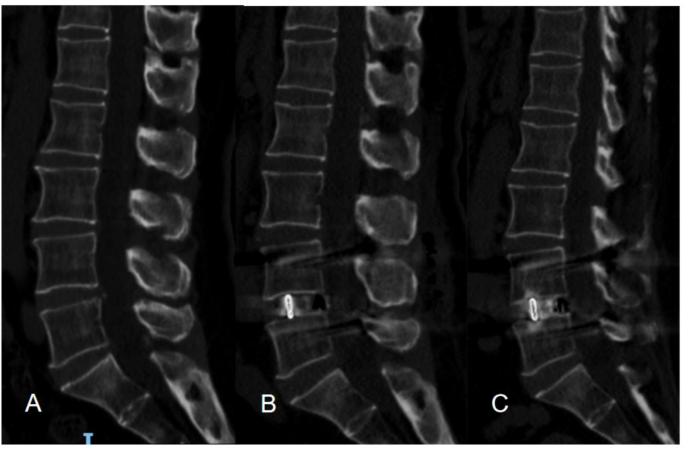

The impact of cage subsidence on clinical outcomes May be evident only with Long-Term Follow-Up

In this study, most cases of cage subsidence OLIF occurred immediately after surgery and the 3–6 month follow-up, consistent with findings by Long Zhao et al.34 For example, a 64-year-old female with chronic back and leg pain underwent L4-5 OLIF for disc herniation. Preoperative assessments showed osteoporosis (bone density T-value of −2.7 and an average L1CT attenuation value of 108.57 HU). Postoperatively, pain relief was significant, with no immediate cage subsidence but slight embedding at L4-5 endplates. At six months, leg pain was resolved, occasional back pain managed with NSAIDs or physical therapy. Imaging revealed cage subsidence between L4-5, with depths of 2.07 mm (L4) and 2.61 mm (L5). (Fig. 4).

A 64-year-old female patient, suffering from recurrent lower back pain for over ten years, accompanied by bilateral leg pain for two years, was diagnosed with lumbar disc herniation and underwent an OLIF surgery at the L4-5 level. (A): Preoperative sagittal lumbar CT; (B): Postoperative lumbar CT, demonstrated satisfactory decompression of the spinal canal, with the cage securely in place. (C): Six-month postoperative lumbar CT showed that the cage had penetrated the endplates, becoming embedded between the lower endplate of L4 and the upper endplate of L5.